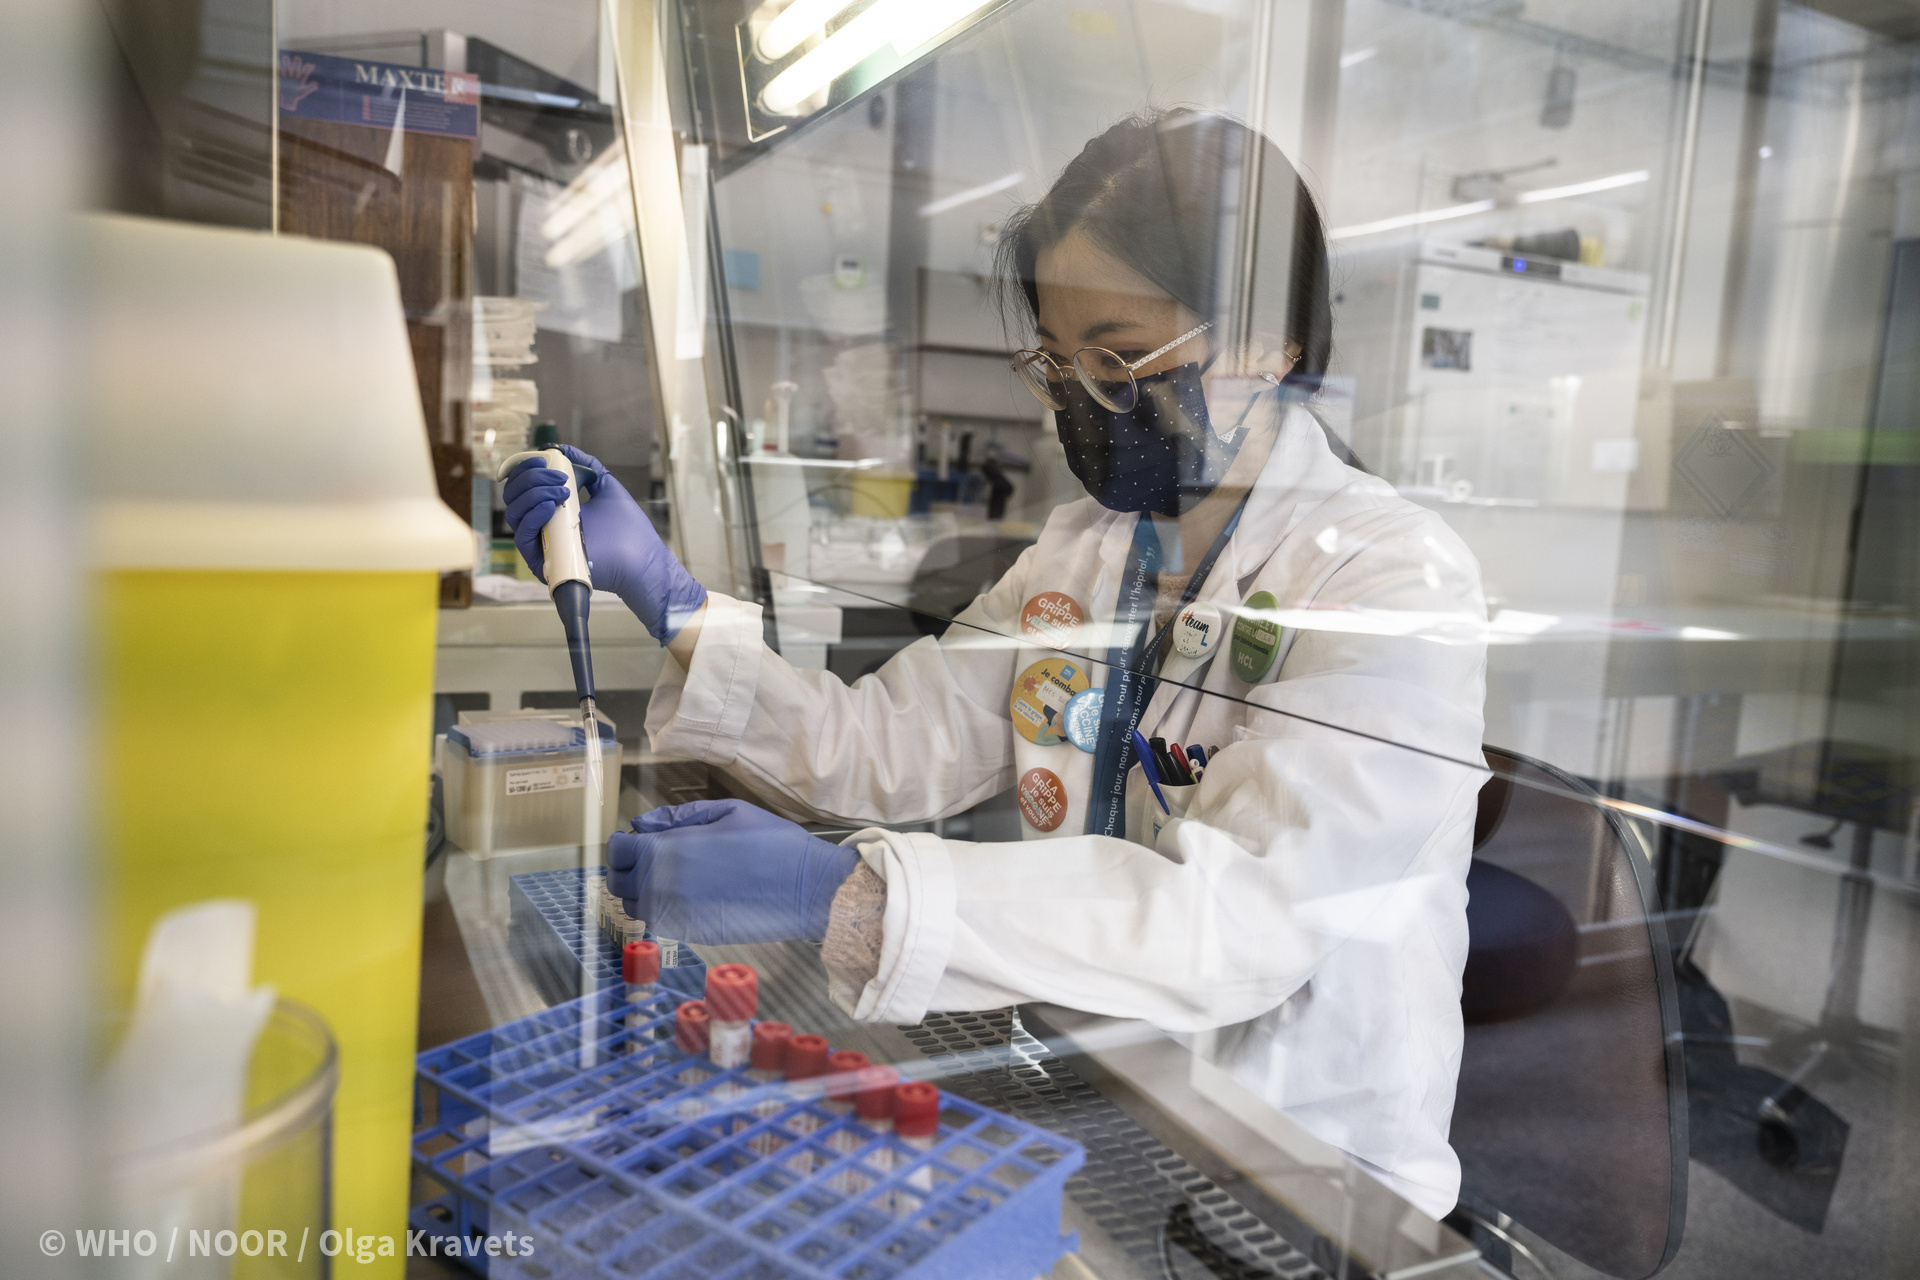

Глобальное бремя болезней: Инфографика и статистика